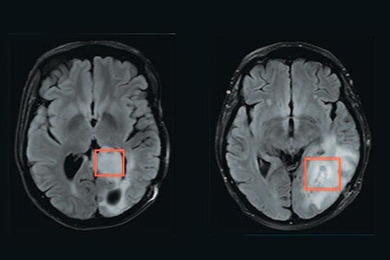

Nanoparticles that enable both MRI and fluorescent imaging could monitor cancer, other diseases.